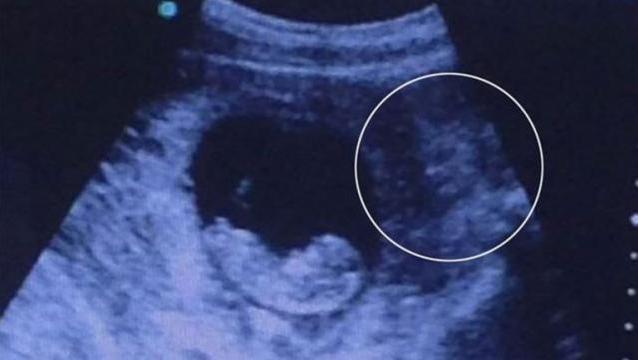

En esta ecografía de un feto de 6 meses, sus padres se vieron muy sorprendidos al divisar un rostro a la izquierda de la fotografía, muy preocupados al no poder reconocerlo.

En esta imagen de ultrasonido, se puede apreciar una extraña criatura acompañando el crecimiento de esta niña: su familia creyó por algún tiempo que un dinosaurio estaba creciendo al mismo tiempo en el vientre de la mujer.